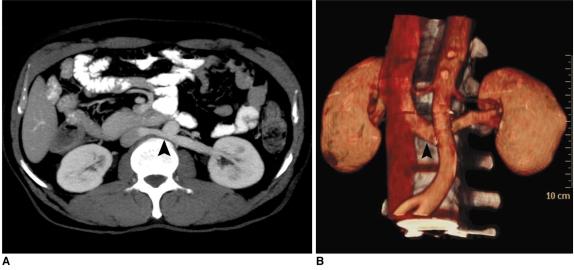

64 通道多排螺旋 CT 血管造影在评估肾血管解剖及可能变异中的应用:影像学研究。

The utility of 64 channel multidetector CT angiography for evaluating the renal vascular anatomy and possible variations: a pictorial essay.

The increased use of laparoscopic nephrectomy and nephron-sparing surgery has prompted the need for a more detailed radiological evaluation of the renal vascular anatomy. Multidetector CT angiography is a fast and accurate modality for assessing the precise anatomy of the renal vessels. In this pictorial review, we present the multidetector CT angiography appearances of the normal renal vascular anatomy and a spectrum of various anomalies that require accurate vascular depiction before undergoing surgical treatment.

摘要

腹腔镜肾切除术和保肾手术的应用日益增多,这促使我们需要更详细地评估肾脏血管解剖结构。多层螺旋 CT 血管造影术是一种快速准确的评估肾脏血管精确解剖结构的方法。在本影像学综述中,我们展示了多层螺旋 CT 血管造影术对正常肾脏血管解剖结构的表现以及一系列需要在手术治疗前准确描述血管的各种异常。